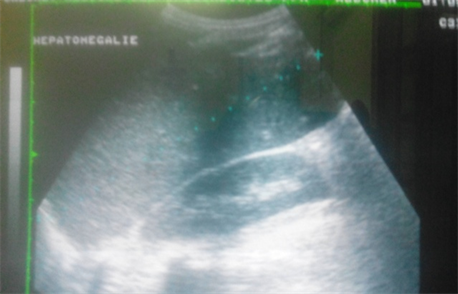

Abdominal ultrasound showed homogeneous hepatomegaly with a liver span measured at 140 mm (Figure 1) and splenomegaly (Figure 2), but signs of portal hypertension or cirrhosis were not detected.

Figure 1. Ultrasound showing Hepatomegaly in our HCV+ patient.